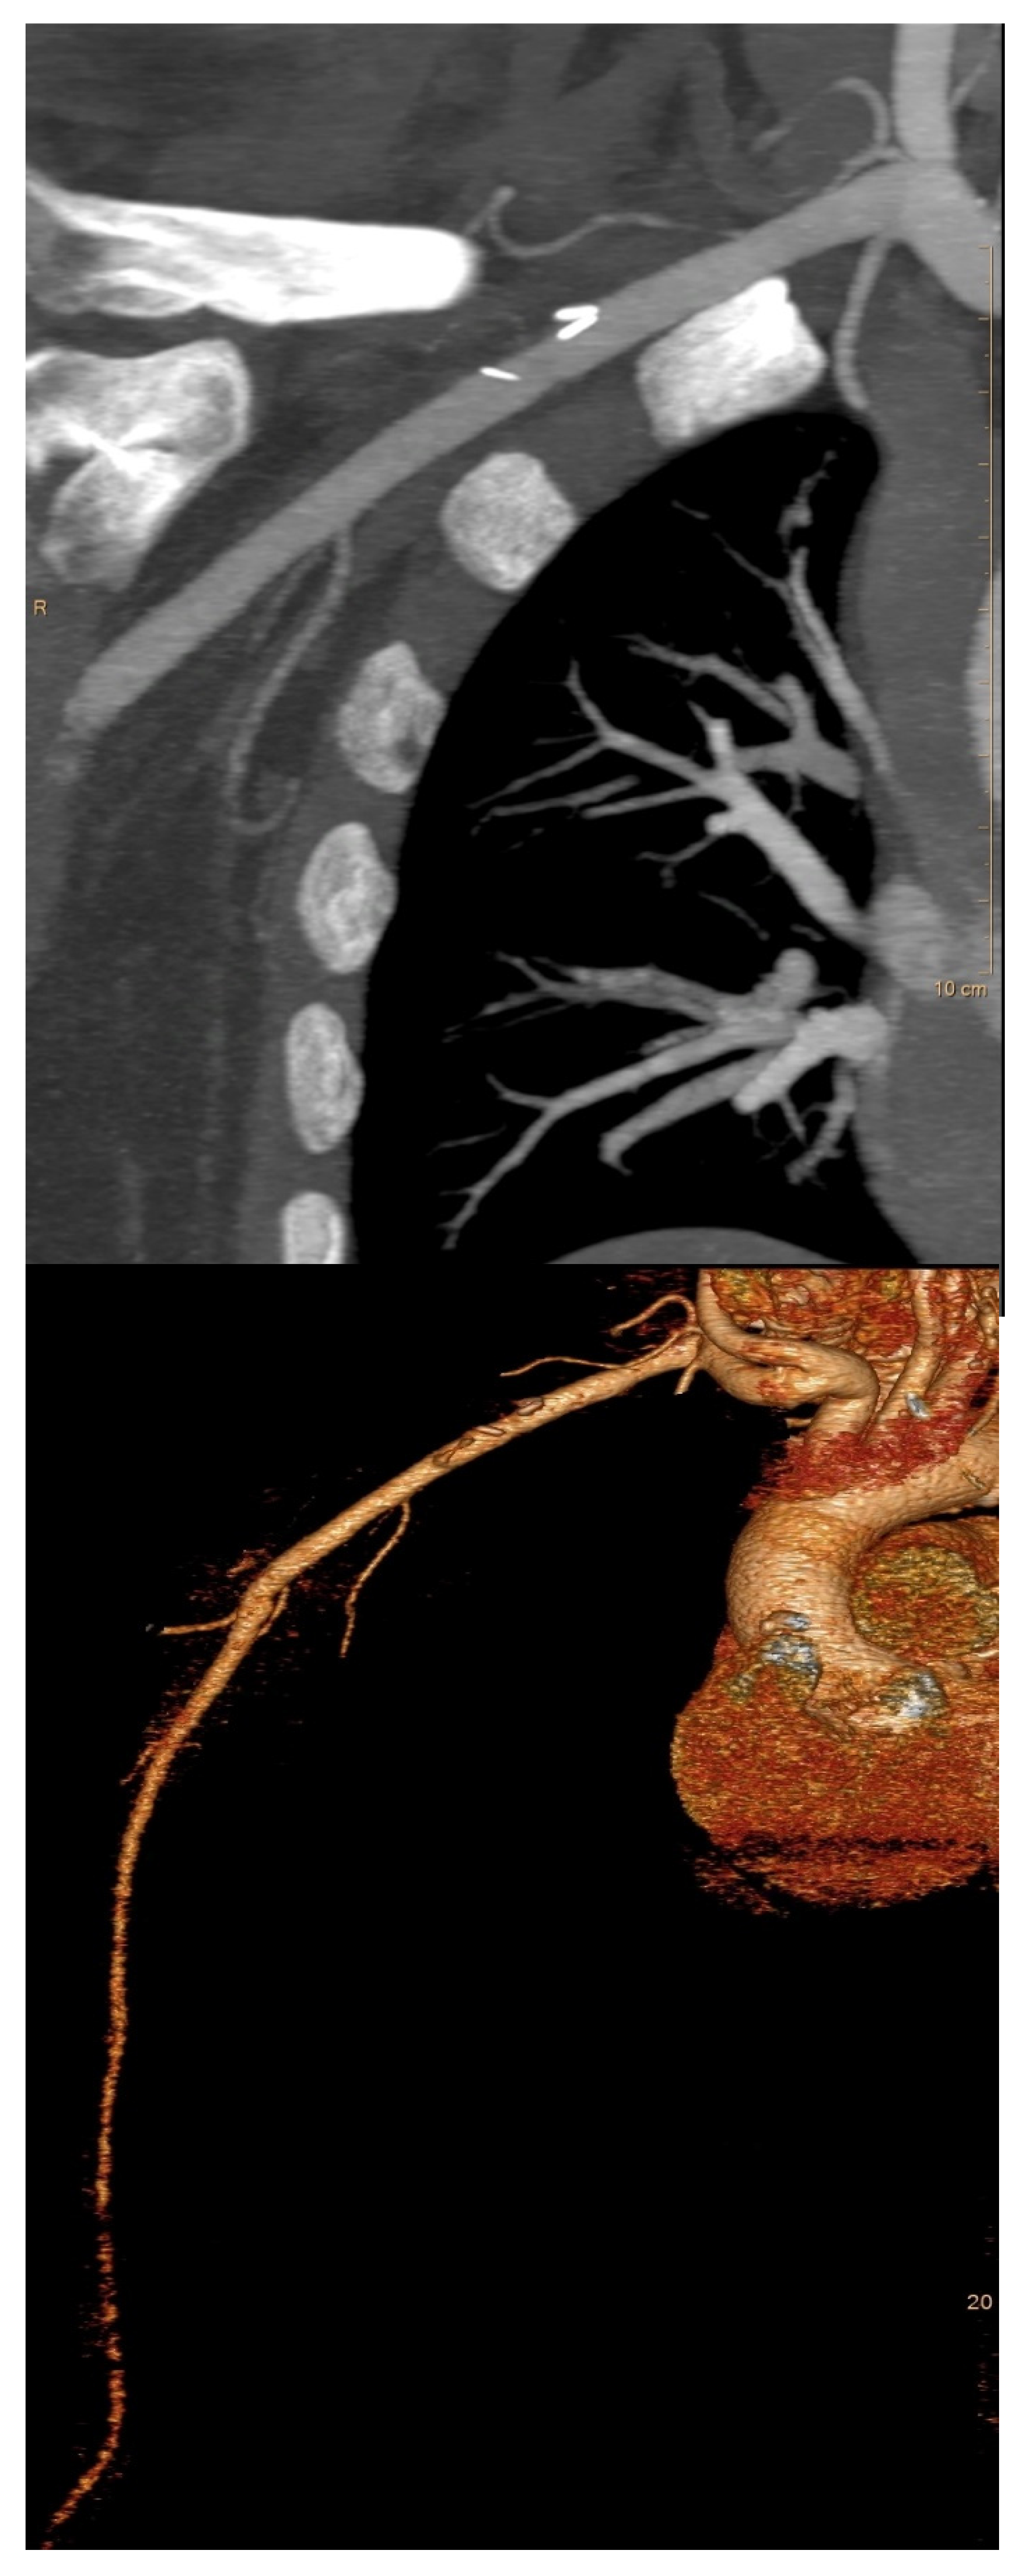

2.2. Preoperative Evaluation

2.4. Surgical Technique